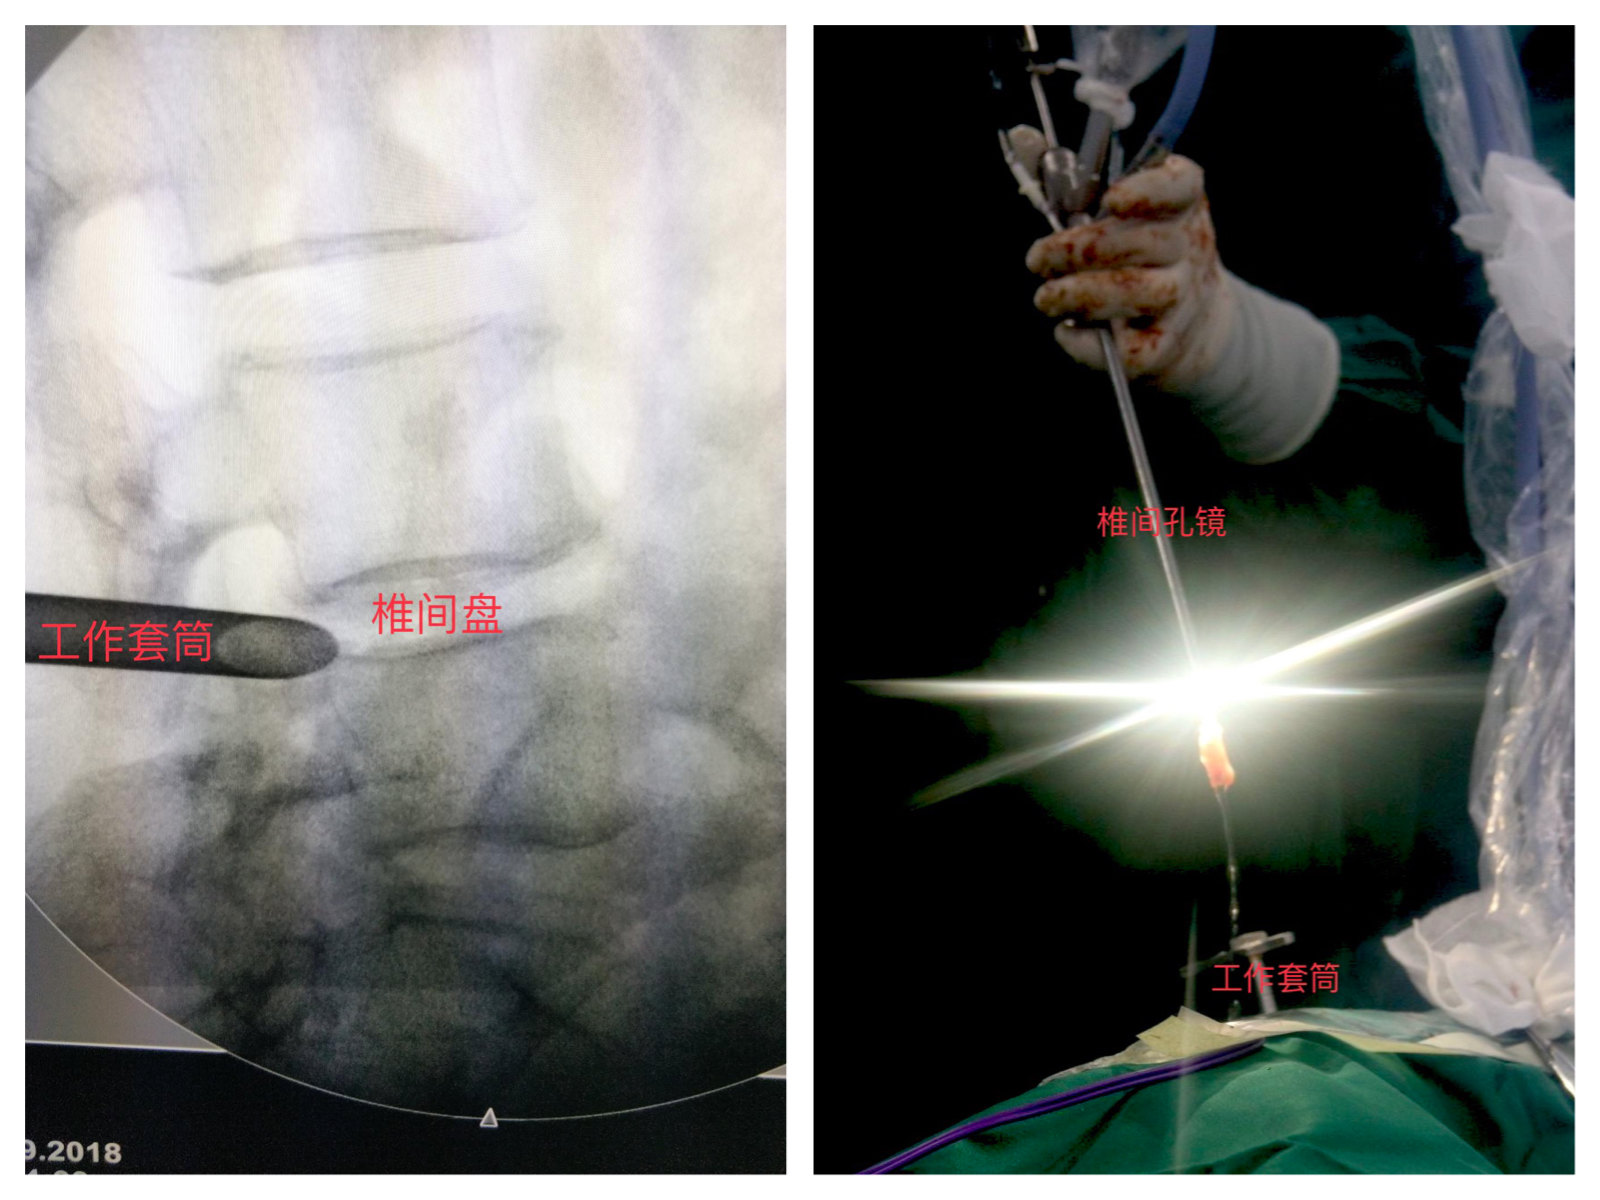

放工作套筒及椎间孔镜

去除阻挡的骨质后,我们会顺着成型后的骨道放入我们最后需要用的工作通道。放好工作通道后,我们顺着放入椎间孔镜,然后将椎间孔镜内的椎管内的影像投射到屏幕上供医生观看并操作取突出间盘。